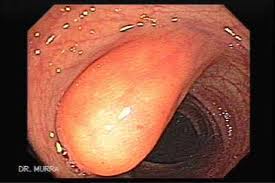

- Pólipos:Un pólipo de colon é unha lesión que protusiona sobre a superficie da mucosa.Moitas neoplasias malignas ou benignas poden adquirir forma de pólipo,a gran maioría son de orixe mucoso e poden dividirse en 2 categorías:hiperplásicos e adenomatosos.

a) tubular:(glandular):ocasionalmente produce hemorraxia.

b) túbulo-velloso

c) velloso:grande,menos frecuente e perigoso.Causan hemorraxia rectal.Precanceroso.

Os hiperplásicos carecen de potencial canceríxeno.As veces hai tendencia familiar a herdar pólipos.